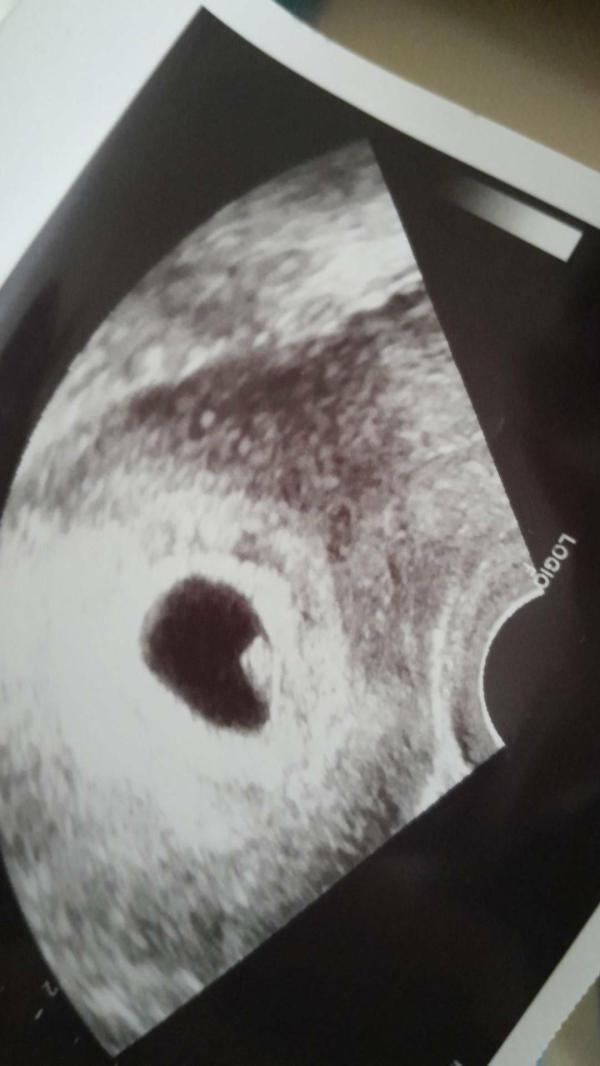

Первое узи. Я его дождалась🙈

По узи срок 6.2 нед , а акушерских 7.2нед

Но врач сказала, что сердцебиение плода на нижней границе нормы 119-120 в минуту.